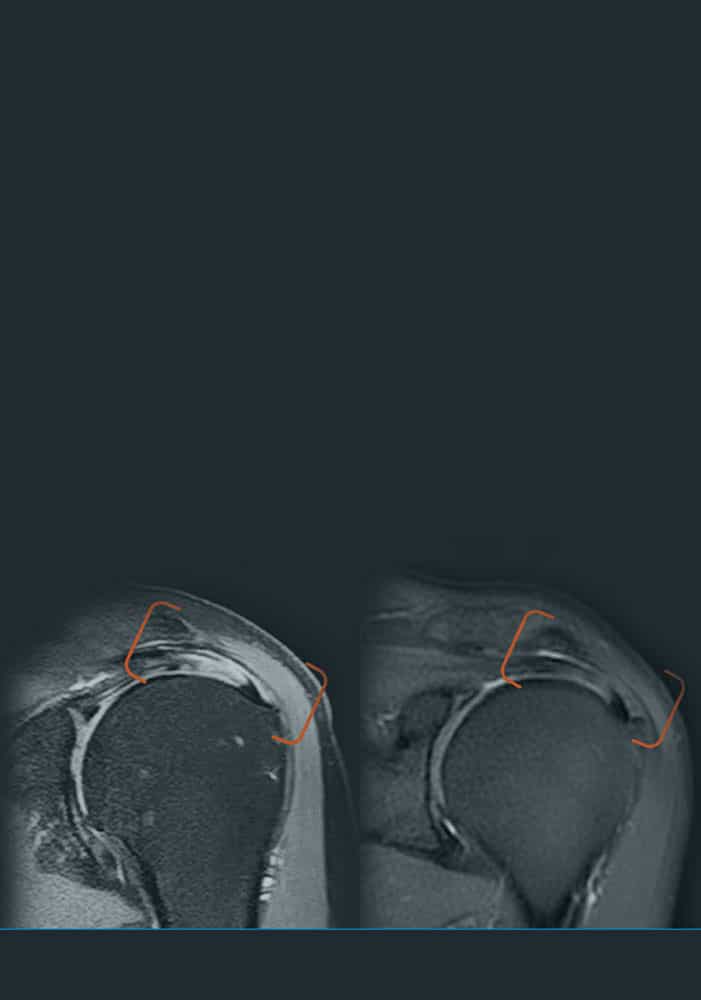

En ITRT hemos demostrado la viabilidad y seguridad de nuestras terapias mediante ensayos clínicos regulados y autorizados por la AEMPS (Agencia Española de Medicamentos y Productos Sanitarios). Una vez superado el ensayo clínico, la AEMPS autoriza el uso del medicamento en pacientes concretos, lo que permite ofrecer tratamientos personalizados con eficacia clínica y capacidad regenerativa demostrada.